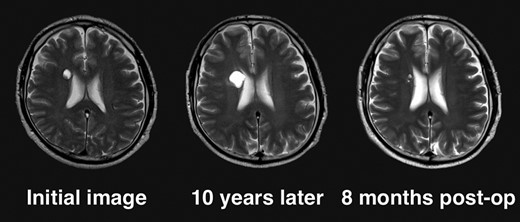

Given the absence of neurological symptoms, the patient was followed conservatively. After a follow-up period of 10 years, the lesion started to increase in size from 10 to 18 mm, accompanied by worsening of headaches. MRI revealed that the increased size of the lesion was attributable to an enlargement of the cystic component and the mural nodule (Fig. 1). A cystic mass with a gadolinium (Gd)-enhancing cyst wall and mural nodule were present. Signal intensity of the cystic component was high on T2-weighted imaging and fluid-attenuated inversion recovery (FLAIR) imaging. The cyst wall and nodule showed low signal intensity on T2*-weighted imaging (Fig. 2). Surgical removal was performed via a trans-cortical approach achieving gross total removal. The cystic component was covered with a transparent thin membrane containing clear yellow fluid, while the mural nodule comprised white, tough tumorous tissue. The lesion showed no invasion into the lateral ventricle. The postoperative course was uneventful, with no complications. No headache and no sign of recurrence have been seen, as of 13 months after surgery (Fig. 2).

Clinical course of the lesion on follow-up neuroimaging. The tumor increased in size during 10 years of follow-up. No recurrence has been seen as of 8 months postoperatively.